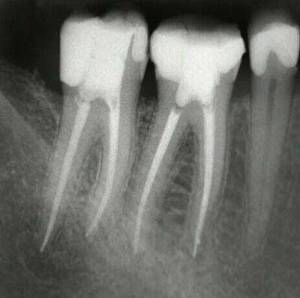

Es una de las técnicas más complejas y laboriosas de la Odontología conservadora, que trata de limpiar y sellar (momificar) los conductos dentarios en dientes con patología pulpar (del nervio) ya sean pulpitis o necrosis pulpar (nervio necrótico).

Es necesario hacer el diagnóstico del estado de la pulpa dentaria (vasos y nervios) que está contenida en el interior del diente para ver si este es viable o vital (vivo) o debe desvitalizarse (endodoncia o tratamiento de conductos).

La endodoncia es uno de los tratamientos más complejos y con mayor riesgo de fracaso de la Odontologia, que requiere unas manos expertas con una técnica muy depurada que sólo puede garantizar un especialista en la materia. Se efectúa el tratamiento biomecánico y la desinfección de los conductos radiculares con diferentes substancias químicas y con limas de diferentes tamaños, para acabar sellando todos los conductos con un material inerte biocompatible que debe llegar hasta el ápice dentario.